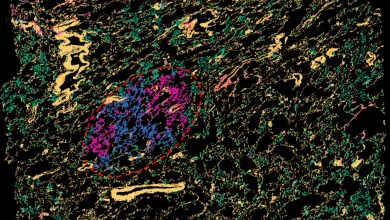

Análise de transcriptômica espacial com resolução superpixel de uma lesão precursora do pulmão humano (borda vermelha), com cores representando diferentes…

Ler Mais » - Notícias